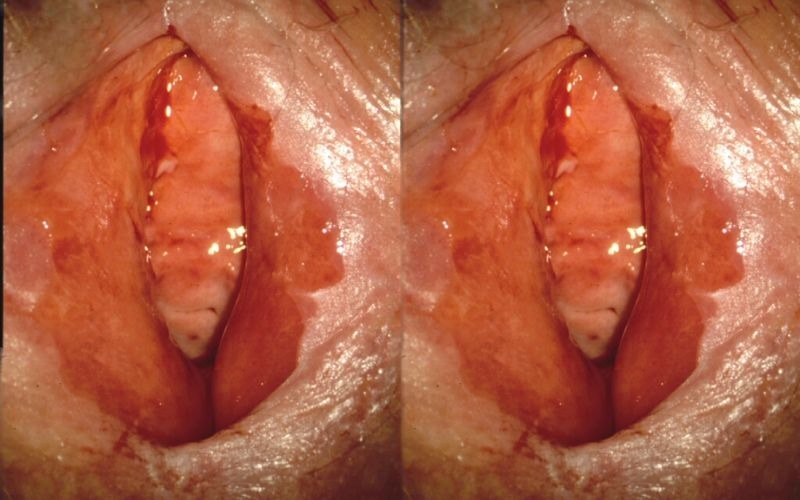

Khí hư bất thường:

- Ra nhiều, có màu vàng, xanh hoặc nâu, kèm theo mùi hôi tanh khó chịu.

→ Đây là một trong những dấu hiệu điển hình nhất của viêm âm đạo, viêm cổ tử cung.

Ngứa rát, sưng đỏ vùng kín:

- Cảm giác nóng rát, khó chịu, thậm chí đau khi đi tiểu hoặc quan hệ tình dục.

→ Đây thường là biểu hiện của nhiễm nấm Candida hoặc viêm âm đạo do vi khuẩn.

Xuất huyết âm đạo bất thường:

- Ra máu ngoài kỳ kinh hoặc sau quan hệ tình dục là dấu hiệu cảnh báo nguy hiểm, có thể liên quan đến tổn thương cổ tử cung, viêm lộ tuyến, thậm chí ung thư cổ tử cung.